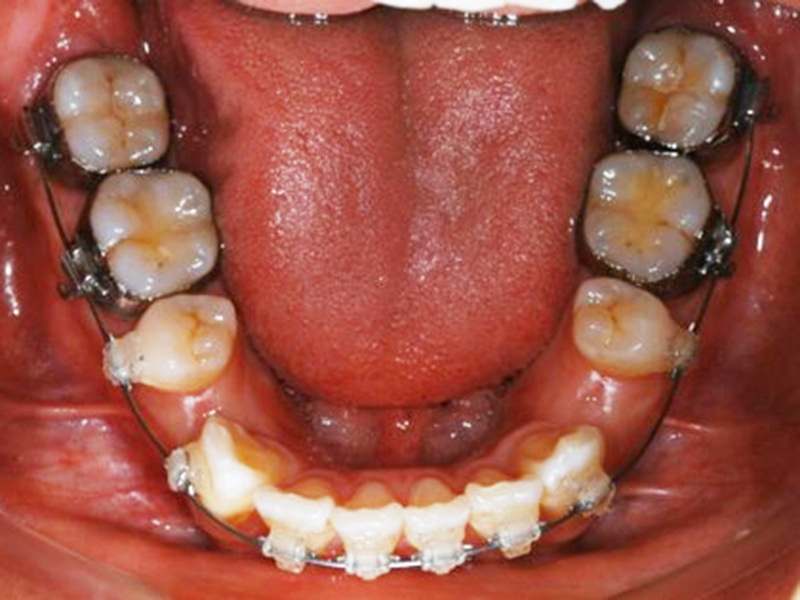

治療中